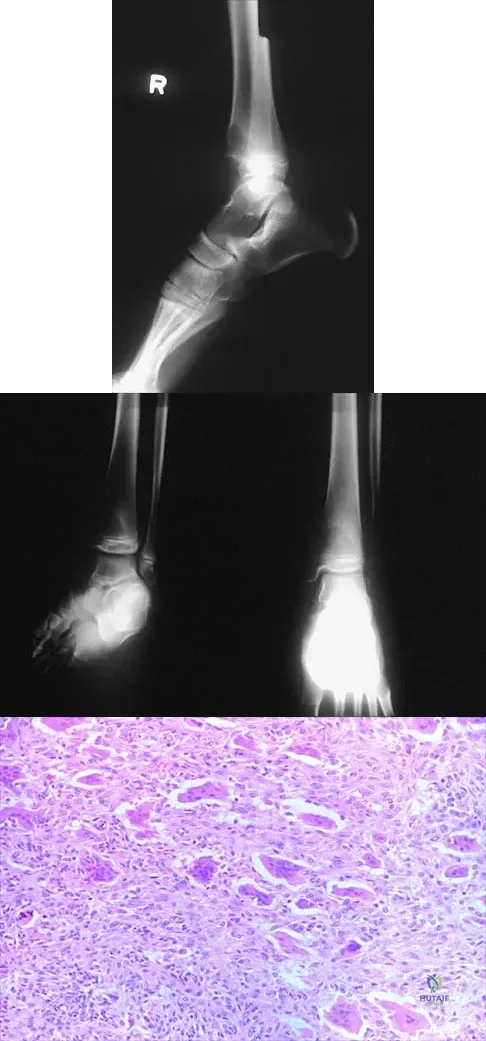

Figures 52a and 52b show the plain radiographs of a 12-year-old girl who has right distal leg pain. She reports that symptoms are present with weight-bearing activities and improve with rest. Examination reveals diffuse tenderness over the distal tibial metaphysis and mild swelling. A photomicrograph of the biopsy specimen is shown in Figure 52c. What is the most likely diagnosis?

Explanation